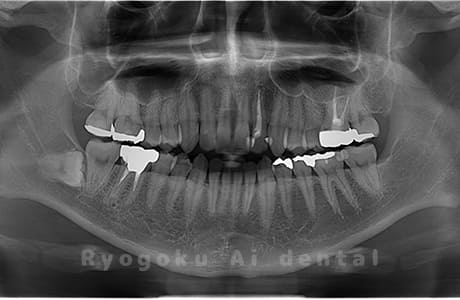

Case03

- 原因

- 上顎、下顎の親知らず

- 治療内容

- 上下4本の親知らずを抜歯したケースです。

<リスク・副作用>

手術後は痛み、腫れ、痺れなどの副作用が生じる場合があります。